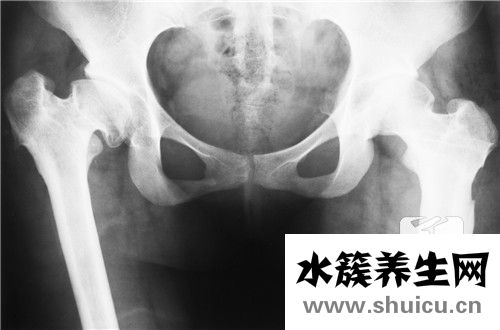

髂骨疼痛常產生于外傷感染或疾病性感染后,老人也可病發,臨床癥狀為突然發熱,髂骨或屁股部分疼痛發脹,常常合拼彎腰痛,髖關及大腿外側痛,以至髖關伸屈不好,病況情況嚴重常焦躁不安乃至呈昏迷情況,亞急性疼痛發病期可持續兩個星期到一個月以上,能夠 開展:

4、限定活動和部分制動系統,限定活動和部分的關鍵目地是緩解疼痛,次之是避免 造成病理性骨折,此方式可選用臥床休息和盆骨懸吊訓練牽引帶,在病情好轉后才可開展活動。